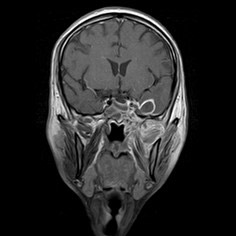

I am just getting ready to change when I see a resident running to me with case files and magnetic resonance images (MRIs) of this day’s patients. And right behind him is a patient’s relative who follows along. I go through the MRI with my ENT friend while he explains this 30-year-old patient, with cerebral abscess and both the maxillary antrum filled with gadolinium, delineating the massive involvement of complete maxillae, palate, all the paranasal sinuses, right orbit, and a cerebral abscess. I stare at the patient's relative who is now gazing at me with hope and desperation in his eyes; I am totally shaken and broken inside.

While the maxillofacial surgeons were more titled towards the contrast-enhanced CT (CECT) scans for diagnostic purposes, as we are more familiar with them, the ENT colleagues insisted on gadolinium-enhanced MRI scans of the paranasal sinuses. On routine discussion of MRIs with my ENT colleague and combining my own surgical experience with it, I observed that very often sequestration formation is a late and inconsistent finding in the palate; more often than not, there is no sequestration, yet the whole of palate was found to be dead with no architectural damage. The cause lies in the angioinvasive nature of the infection where multiple fungal thrombi block arterial supplies from various directions almost together, like guerrilla warfare against the immunologically suspended host. Hence, the only visible evidence of involvement and its extent before intervention are the MRI and surgeon’s own clinical judgement as she moves slowly towards exposure and debridement.